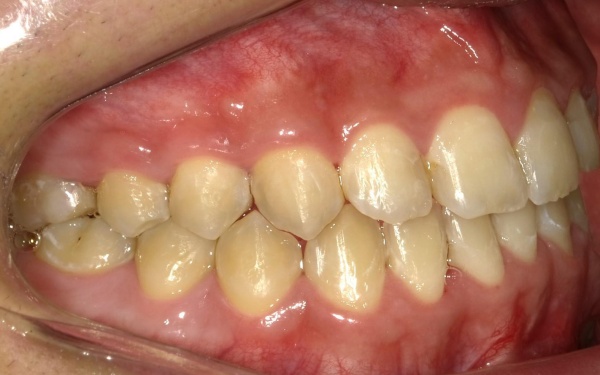

10代男性 顎変形症が原因で下顎がずれて非対称になっていた噛み合わせをサージェリーファースト法を併用した矯正治療で改善した症例

治療後

治療後画像

治療後画像 治療後画像 治療後画像 治療後画像 治療後画像 治療後画像